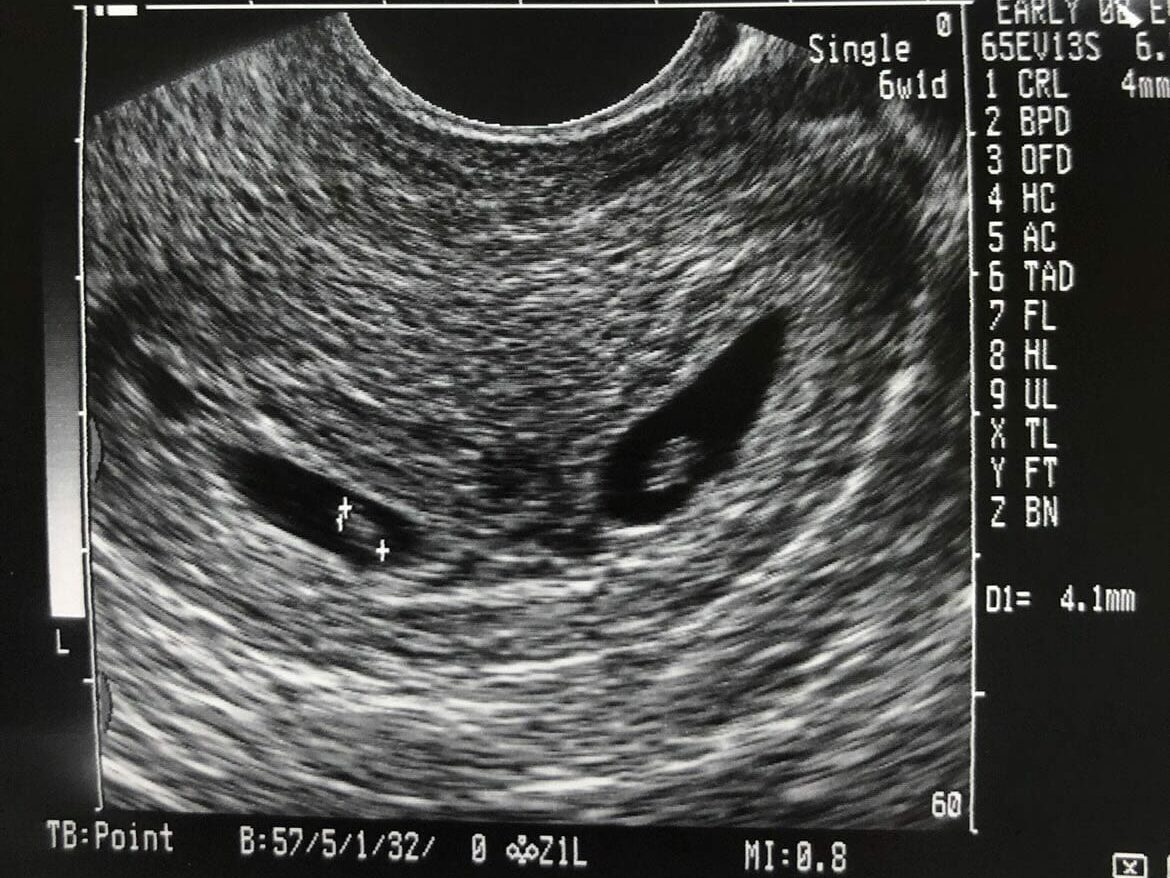

Had my first ultrasound at 6.5 weeks. The tech said she was SURE it was just one baby. (I had asked if it was twins) 4 weeks later same tech does the scan and I think she was more shocked than I was that there were 2 babies on the screen!

Ultrasound at 6 weeks only 1 baby… 16 weeks 2 babies.

Twins can typically be detected on ultrasound during the first trimester, usually around 6 to 8 weeks of gestation. In some cases, healthcare providers may be able to identify the presence of twins even earlier, especially with advanced ultrasound technology. The ability to visualize twins on an ultrasound depends on factors such as the clarity of the image, the position of the embryos, and the experience of the ultrasound technician.